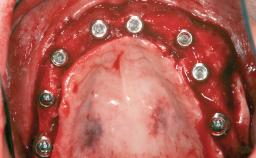

A woman in her mid-fifties was referred by a dental student for dental implant placement. Both posterior segments of the mandible had been edentulous for more than 4 years, the only residual tooth being the right lower first premolar. The patient had used a removable partial denture but was not entirely satisfied with its function. The clinical examination revealed a sharp edentulous ridge in both posterior segments of the mandible, and the patient was told that it would not be possible to insert implants into this thin edentulous ridge without significant augmentation of the alveolar ridge. Her medical history revealed no significant findings and no underlying disease that might have complicated surgical procedures. During the presurgical examination, the patient reported that she was a little apprehensive about bone grafting. After being informed about the surgical procedures and potential postoperative complications, she accepted the proposed surgical plan of bone grafting and subsequent placement of implants.

# of Implants 5

Type of Implants One-Piece

Bone Augmentation Horizontal|Staged